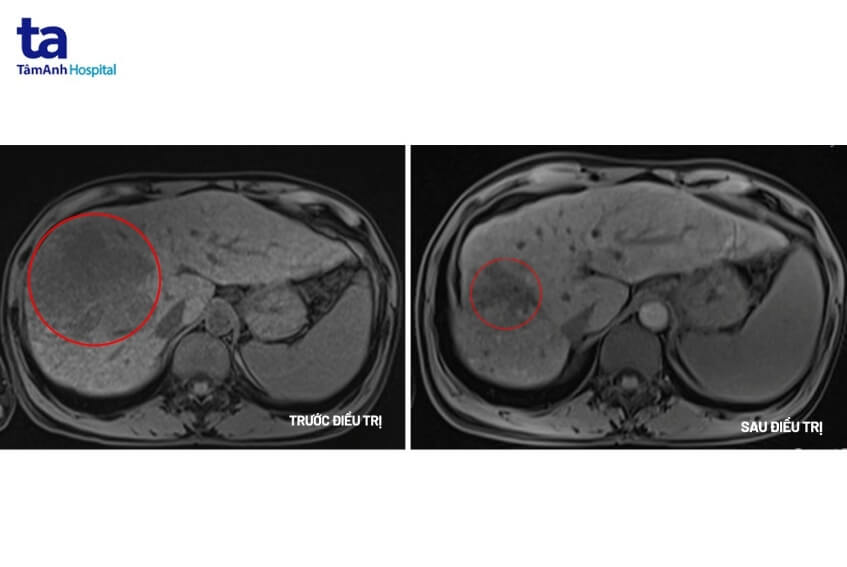

Qua khám lâm sàng thấy có dấu hiệu của ung thư gan, tiến sĩ Khiêm chỉ định người bệnh thực hiện một số xét nghiệm để khẳng định. Xét nghiệm chỉ điểm ung thư gan cho thấy chỉ số AFP là 9412ng/mL (người bình thường chỉ số này là < 10ng/mL); AFP L3 81,3% (ngưỡng bình thường <10%); PIVKA II=56661 mAu/mL (ngưỡng bình thường <40 mAu/mL). Trên MRI cho thấy khối u lớn ở gan phải với kích thước 10x10x12cm có tính chất HCC, huyết khối tĩnh mạch cửa và xơ gan. Kết quả cho thấy người bệnh mắc ung thư gan giai đoạn muộn.

Sau 12 chu kỳ (khoảng 6 tháng) điều trị phác đồ miễn dịch kết hợp kháng thể đơn dòng, khối u gan đã giảm hơn 50% kích thước, người bệnh không xuất hiện triệu chứng đau, không có dịch ổ bụng, chức năng gan thận trở lại bình thường, cải thiện chất lượng cuộc sống. Bệnh nhân tiếp tục được điều trị và theo dõi chặt chẽ để nâng cao hiệu quả.